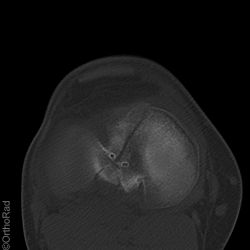

Tibiakopffraktur (nicht disloziert)